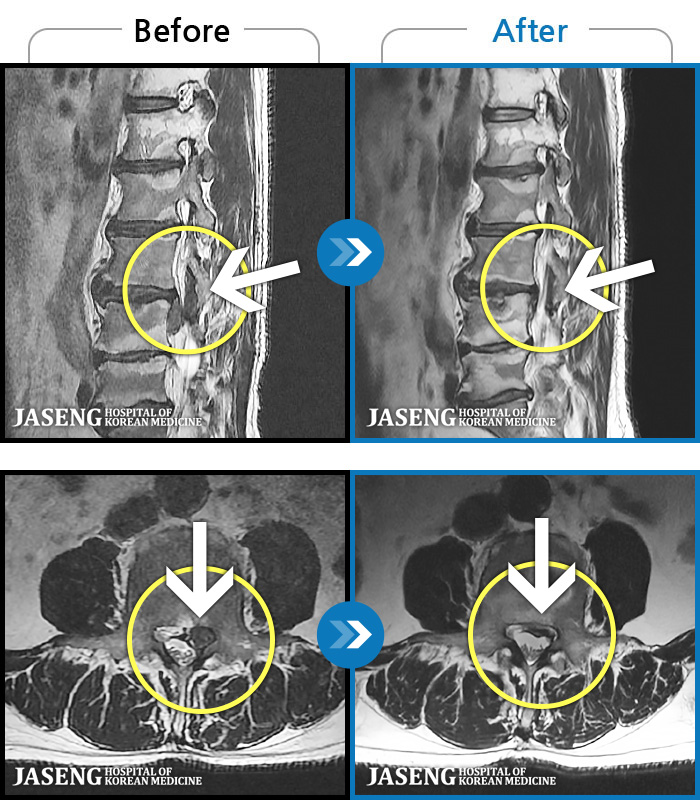

요추 추간판 탈출증을 진단받은 입원 환자의 보완대체의학 통합치료의 장기 효과

Before

After

처음 내원 시 허리와 좌측 다리 통증이 심한 상태로 내원하셨습니다.

2012.05.11 ~ 2022.08.29